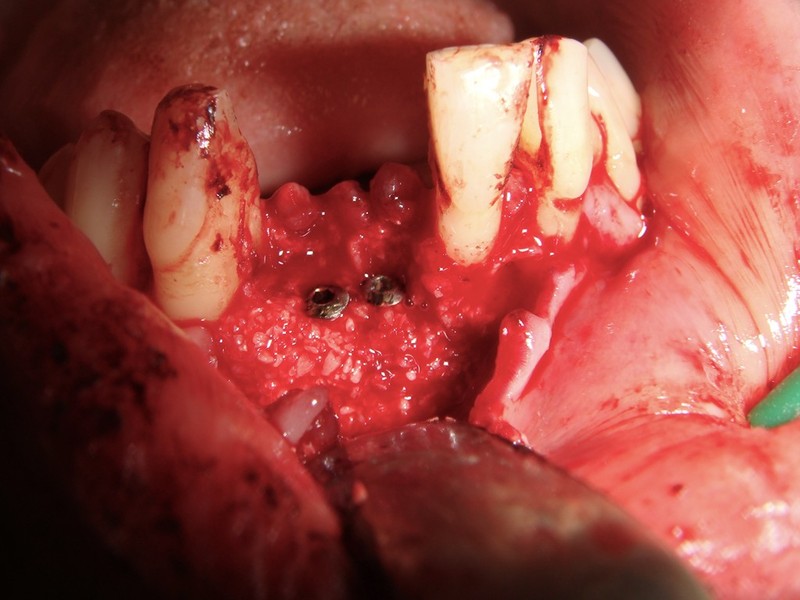

Impianti post-estrattivi complessi con innesto osseo